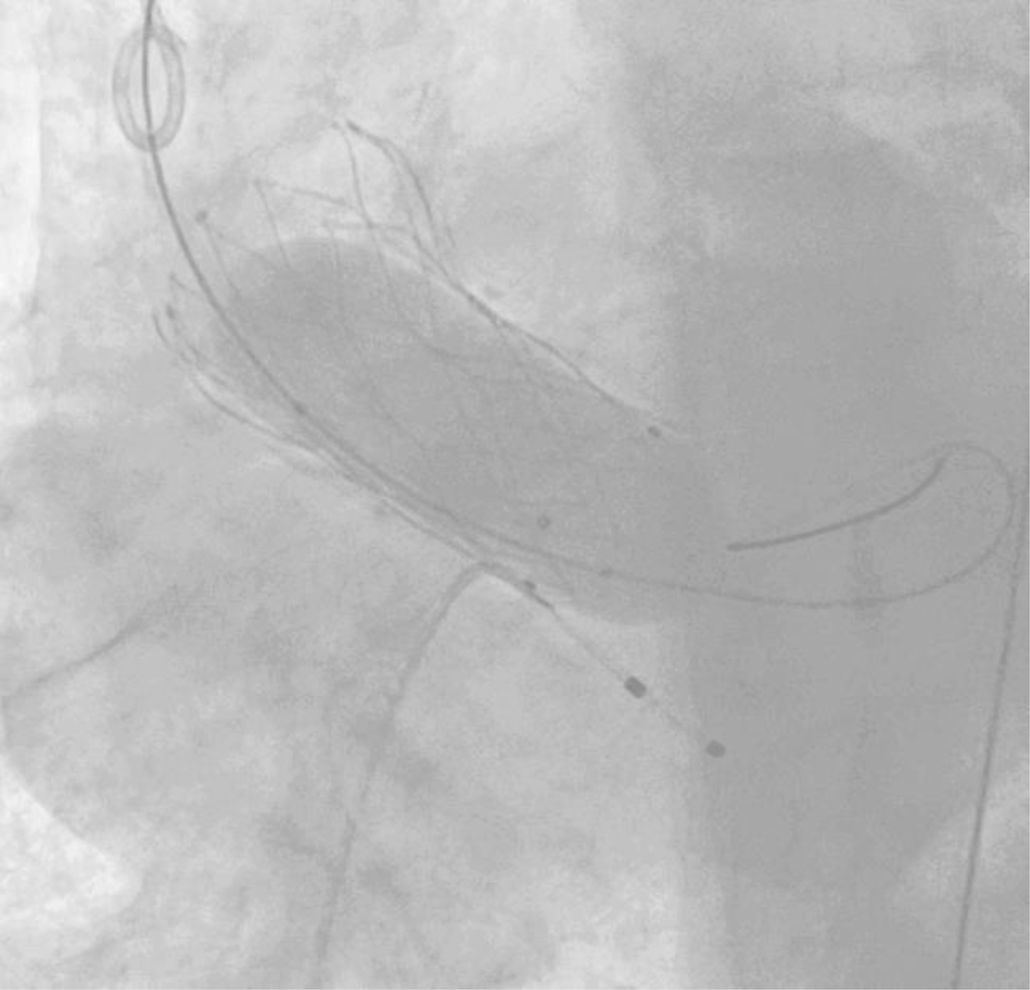

Post-dilatación (fig. 2)Cuando se trata de dirimir cuáles son los resultados clínicos de pacientes sometidos o no a post-dilatación, la evidencia de la que disponemos38-45 nace, una vez más, de estudios no aleatorizados y sesgados. Ello explica la disparidad de sus conclusiones y traduce la necesidad de interpretarlas con cautela.

Existen numerosos escenarios que motivan el planteamiento de la post-dilatación tras el implante de una TAVI. Quizá el más importante (por su elevada frecuencia y repercusión negativa) sea la reducción de la severidad de una RPV, pues el baloneo promueve una expansión óptima de la prótesis (figs. 3 y 4). Con ello, también se consiguen un aumento del área valvular efectiva, una disminución de los gradientes y, en consecuencia, una reducción del mismatch (que se ha asociado a una mayor incidencia de trombosis valvular clínica y subclínica)46.